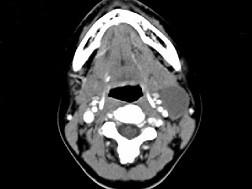

问题 女,16岁,发现左颈部肿块两年,CT如图所示,最可能的诊断为 ( )

选项 A、左侧鳃裂囊肿 B、囊性转移癌 C、咽部神经鞘瘤 D、咽旁脓肿 E、囊状水瘤

答案 A